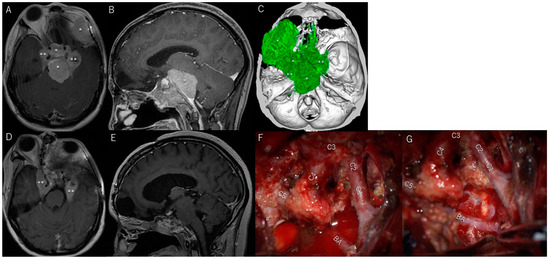

3.6. Illustrative Patient Cases

| 5 | y | n | anterolateral triangle | Totally | 1 | n | n | n | brain swelling/complete recovery | |

| 5 | n | n | y | 11 | resection + IMRT 60 Gy/30 fr | |||||